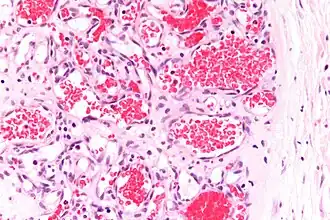

A precise history of the growth characteristics of the IH can be very helpful in making the diagnosis. In the first 4 to 8 weeks of life, IHs grow rapidly with primarily volumetric rather than radial growth. This is usually followed by a period of slower growth that can last 6–9 months, with 80% of the growth completed by 3 months. Finally, IHs involute over a period of years.[36] The exceptions to these growth characteristics include minimally proliferative His, which do not substantially proliferate[35] and large, deep IHs in which noticeable growth starts later and lasts longer.[36] If the diagnosis is not clear based on physical examination and growth history (most often in deep hemangiomas with little cutaneous involvement), then either imaging or histopathology can help confirm the diagnosis.[33][37] On Doppler ultrasound, an IH in the proliferative phase appears as a high-flow, soft-tissue mass usually without direct arteriovenous shunting. On MRI, IHs show a well-circumscribed lesion with intermediate and increased signal intensity on T1- and T2-weighted sequences, respectively, and strong enhancement after gadolinium injections, with fast-flow vessels.[33] Tissue for diagnosis can be obtained via fine-needle aspiration, skin biopsy, or excisional biopsy.[38] Under the microscope, IHs are unencapsulated aggregates of closely packed, thin-walled capillaries, usually with endothelial lining. Blood-filled vessels are separated by scant connective tissue. Their lumina may be thrombosed and organized. Hemosiderin pigment deposition due to vessel rupture may be observed.[39] The GLUT-1 histochemical marker can be helpful in distinguishing IHs from other items on the differential diagnosis, such as vascular malformations.[34]